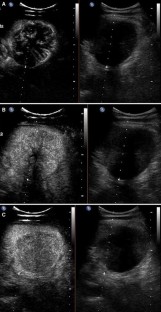

Fig. 2